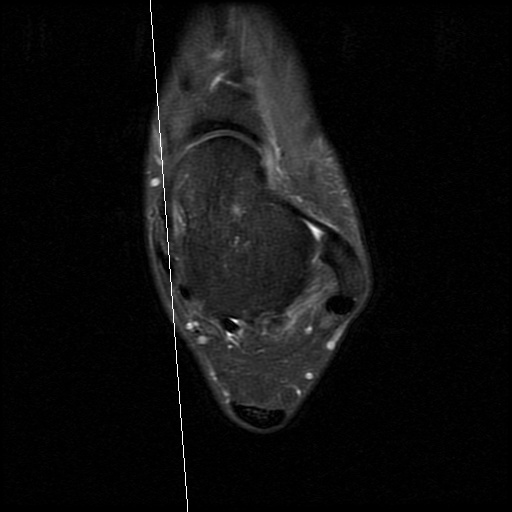

患者,男,28岁,有踝关节扭伤史,患者10天前扭伤致左踝疼痛伴活动受限。查体:左踝关节轻度肿胀,关节缘广泛性压痛,未扪及骨擦音及骨擦感,局部皮肤无瘀青、无皮损,外翻应力试验阳性,抽屉试验阳性,肢端感觉及血运正常。

患者行关节镜下距腓前韧带修补术,术后恢复良好。